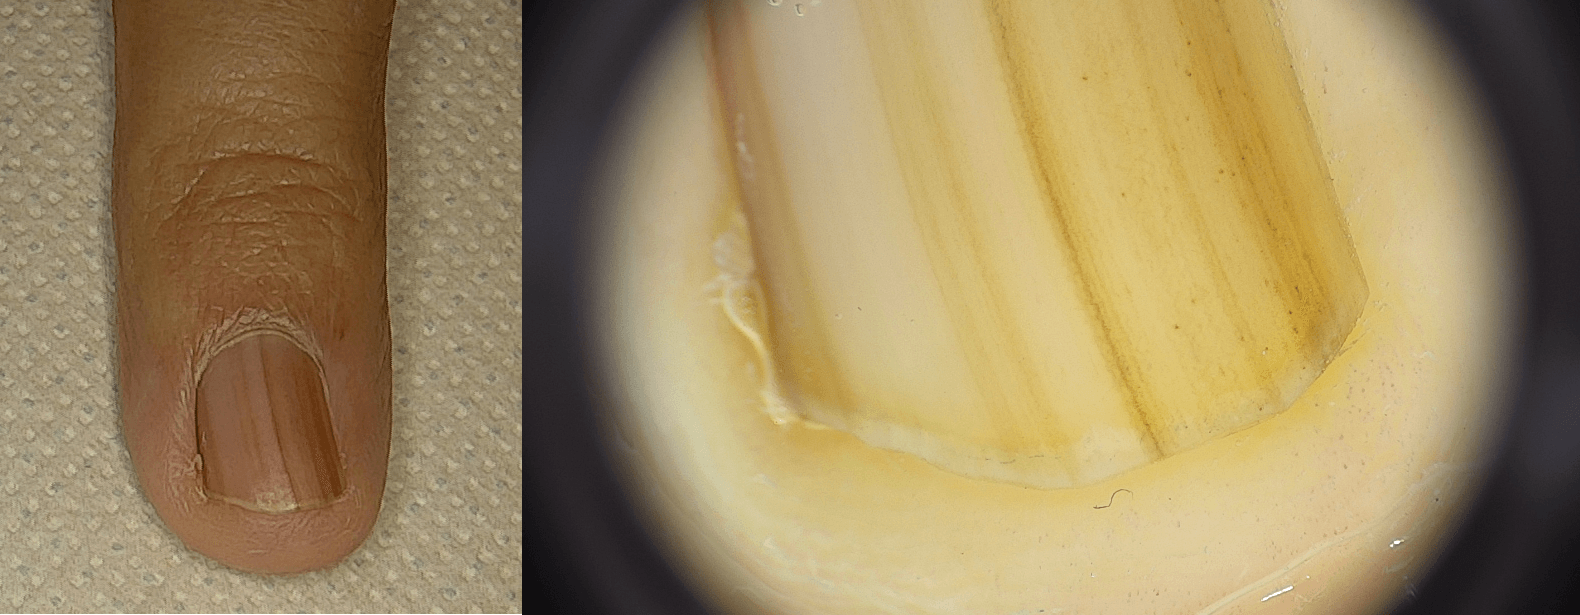

La videodermatoscopia digitale a epiluminescenza consente l’osservazione ad alto ingrandimento di nei e altre lesioni pigmentate o non pigmentate, documentandone struttura, colore e pattern vascolari.

La mappatura digitale dei nevi crea un archivio fotografico confrontabile nel tempo, utile a rilevare microvariazioni che possono suggerire ulteriori indagini o l’indicazione all’asportazione. Lo studio utilizza sistemi ad alta definizione (es. piattaforma FotoFinder) con acquisizione di immagini cliniche e dermatoscopiche, associazione a sedi topografiche e generazione di report utili alla discussione diagnostica e alla programmazione del follow-up.

Per il melanoma, la tempestività diagnostica è cruciale. La dermatoscopia digitale aiuta a identificare criteri di atipia, regressione o crescita irregolare non visibili a occhio nudo. In presenza di segni sospetti si procede a escissione diagnostica con valutazione istologica completa. La chirurgia segue margini proporzionati allo spessore istologico; il calendario dei controlli viene definito in funzione di istotipo, sede, spessore, familiarità e fototipo, con chiare indicazioni su fotoprotezione e autocontrollo.